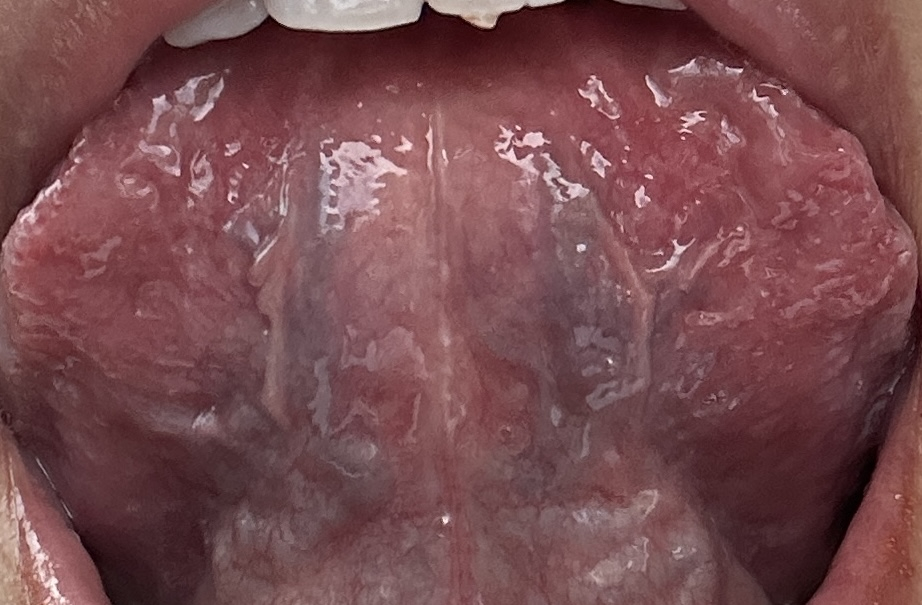

请您看一下可能高脂高蛋白的东西吃多了,同时主食和蔬菜吃得太少,以致于肝胆湿热下注于肾,可能有胆肾结石了。

高脂低碳水饮食的严重的副作用,除了容易导致:胆结石、肾结石、骨质疏松之外,

还会严重影响情绪稳定,会引起:疲劳、沮丧、暴躁、易怒、健忘、失眠、幸福感低……

主因之一是:过多摄入的脂肪代谢之后会产生过多的酮体,从而干扰中枢神经系统功能的稳定。

【蔬菜】是能”疏通郁结“的植物茎叶,能助肠道和肾脏排泄毒素。